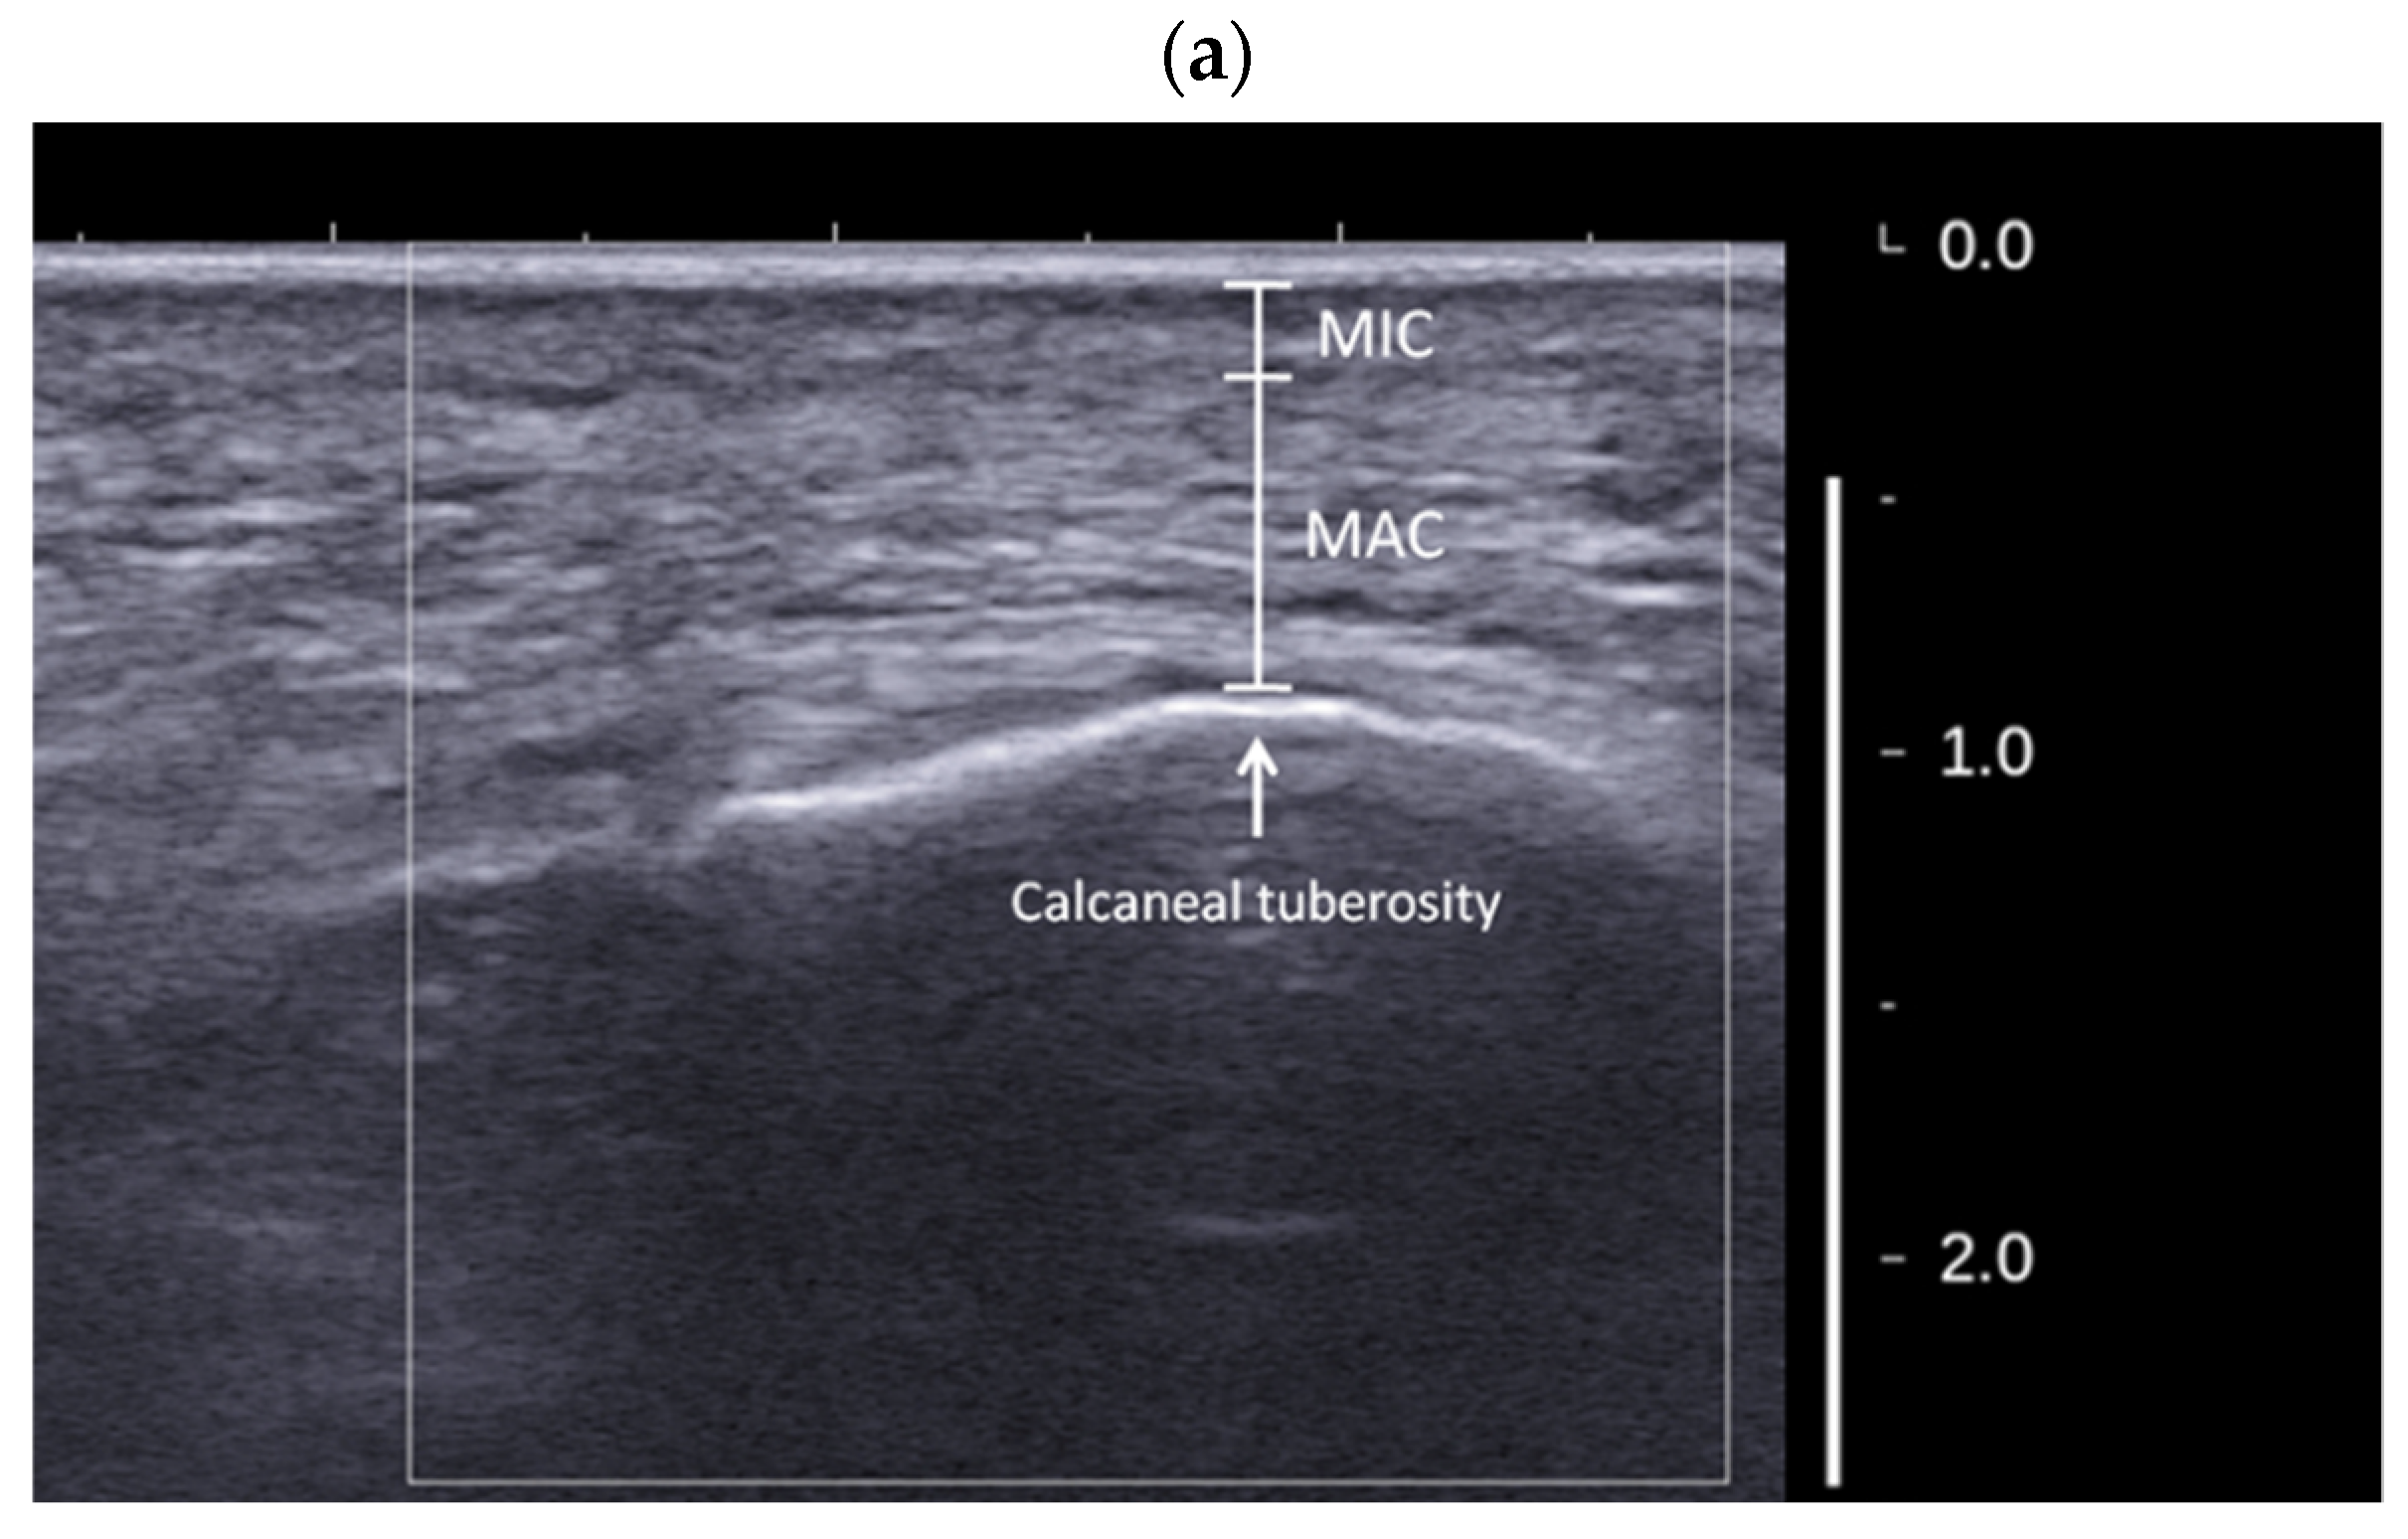

- Hsu, C.C.; Tsai, W.C.; Wang, C.L.; Pao, S.H.; Shau, Y.W.; Chuan, Y.S. Microchambers and macrochambers in heel pads: Are they functionally different? J. Appl. Physiol. 2007, 102, 2227–2231. [Google Scholar] [CrossRef]

- Hsu, C.C.; Tsai, W.C.; Hsiao, T.Y.; Tseng, F.Y.; Shau, Y.W.; Wang, C.L.; Lin, S.C. Diabetic effects on microchambers and macrochambers tissue properties in human heel pads. Clin. Biomech. 2009, 24, 682–686. [Google Scholar] [CrossRef]

- Wu, C.H.; Lin, C.Y.; Hsiao, M.Y.; Cheng, Y.H.; Chen, W.S.; Wang, T.G. Altered stiffness of microchamber and macrochamber layers in the aged heel pad: Shear wave ultrasound elastography evaluation. J. Formos. Med. Assoc. 2018, 117, 434–439. [Google Scholar] [CrossRef] [PubMed]